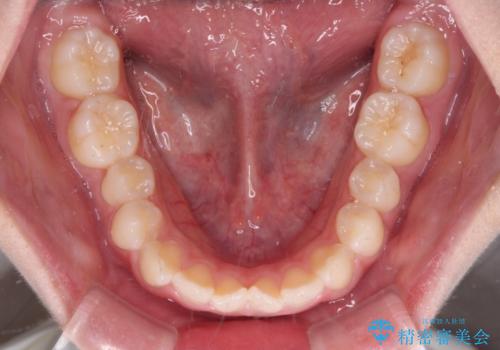

- 前歯のデコボコを気にして来院された高校生の患者様です。

捻れた前歯が前方に飛び出している点も気になっており、目立たない装置を希望されたため、インビザラインを用いて矯正治療を行うこととしました。

上下ともに少し捻れが残っていたため、治療の継続を提案しましたが、本人も親御さんも満足とのことで、治療を終えました。

捻れの改善により突出感も改善されました。